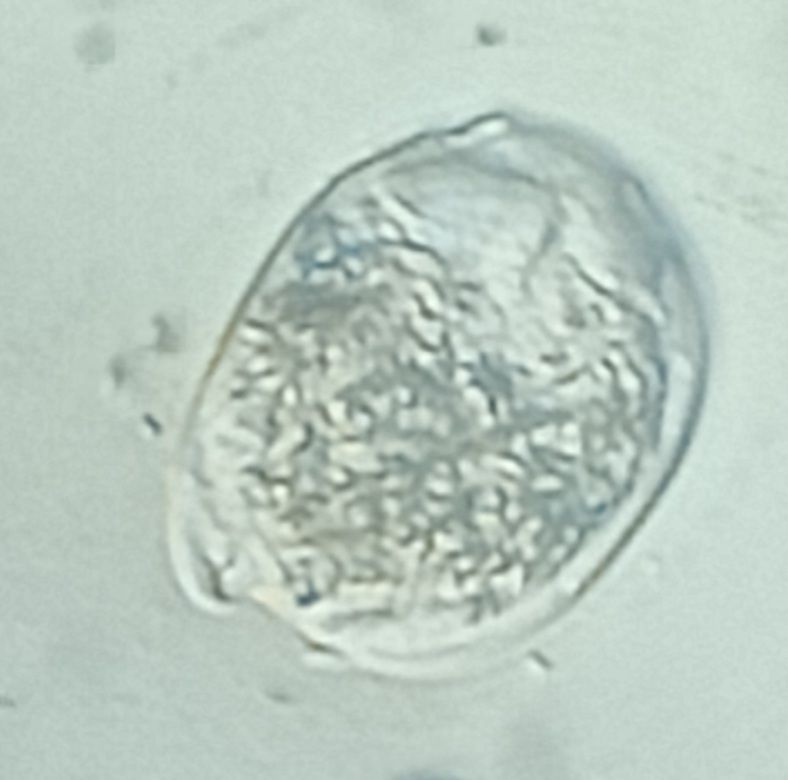

I am Dr.S.Meignanalakshmi, working as Professor, at the Directorate of Centre for Animal Health Studies, TANUVAS, Chennai-51. Working on Foldscope project on "Foldscope for diagnosis of Rumen Acidosis and parasitic infections in cattle" sanctioned by DBT